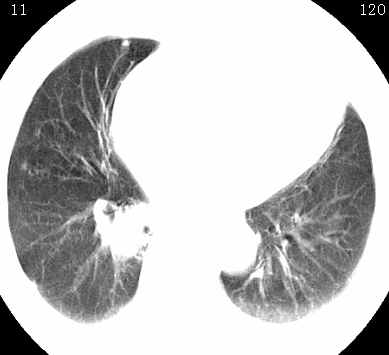

标题: CT26680:肺部右下肺静脉干结节的界定 [打印本页]

标题: CT26680:肺部右下肺静脉干结节的界定

经追查说有支扩咯血病史,但不确定

考虑1、周围型肺癌,2肺静脉畸形,前者可能大,建议增强检查。

考虑1、周围型肺癌,2肺静脉畸形,前者可能大,建议增强检查。支持!

不排除右肺下叶周围型肺癌可能。